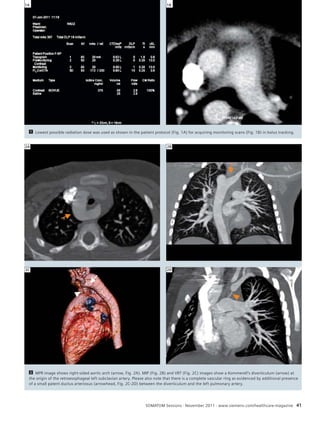

40 Flash Scanning for Pediatric Aortic

Abnormalities without Sedation at

0.6 mSv